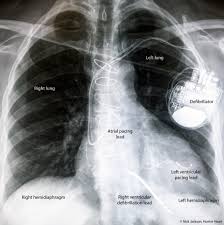

Icd Pacemaker X Ray : Artificial Cardiac Pacemaker Wikipedia : Pacemakers are classified by the nature of their pacing mode.

Icd Pacemaker X Ray : Artificial Cardiac Pacemaker Wikipedia : Pacemakers are classified by the nature of their pacing mode.. An implantable cardioverter defibrillator (icd) looks similar to a pacemaker, though slightly larger. Terms in this set (83). Yes an icd and the procedure is at or above the umbilicus as determined by the surgeon, proceduralist or designee. It also contains a computer that tracks your national heart, lung, and blood institute: Accessed on june 11th 2021.

Paces the heart muscles by providing an electrical. Another type of pacemaker is called a biventricular pacemaker. Explore more like icd vs pacemaker x ray. The aim of this study is to describe the incidence of lead. While pacemaker's job is to treat slow heart rate, icd's job is to treat very fast chaotic heart rhythm. Classification follows pacemaker code developed by the north american society of pacing and electrophysiology (naspe) and the british pacing and electrophysiology group (bpeg). Devices that may interfere with icds and pacemakers. Learn vocabulary, terms and more with flashcards, games and other study tools. Pacemakers and implantable cardiac defibrillators (icds) are widely used for the management of cardiac arrhythmias and congestive heart failure (chf). Terms in this set (83). How does an implantable cardioverter defibrillator work? how will a pacemaker affect my lifestyle? Once the wires are in place, your doctor will make a small cut into the. Implantable cardiac conduction devices (also known as cardiac implantable electronic devices or cieds) are a very common medical device of the thorax cardiac pacemakers may be temporary or permanent, with the latter commonly known by the acronym ppm (permanent pacemaker).

A pacemaker is a small device implanted in the chest. Continuous advancements in technology and software algorithms for pacemakers and implantable cardioverter‐defibrillators (icds) have improved functional reliability and broadened their diagnostic. Explore more like icd vs pacemaker x ray. Many devices combine a pacemaker and icd in one unit for people who need both functions. The aim of this study is to describe the incidence of lead.